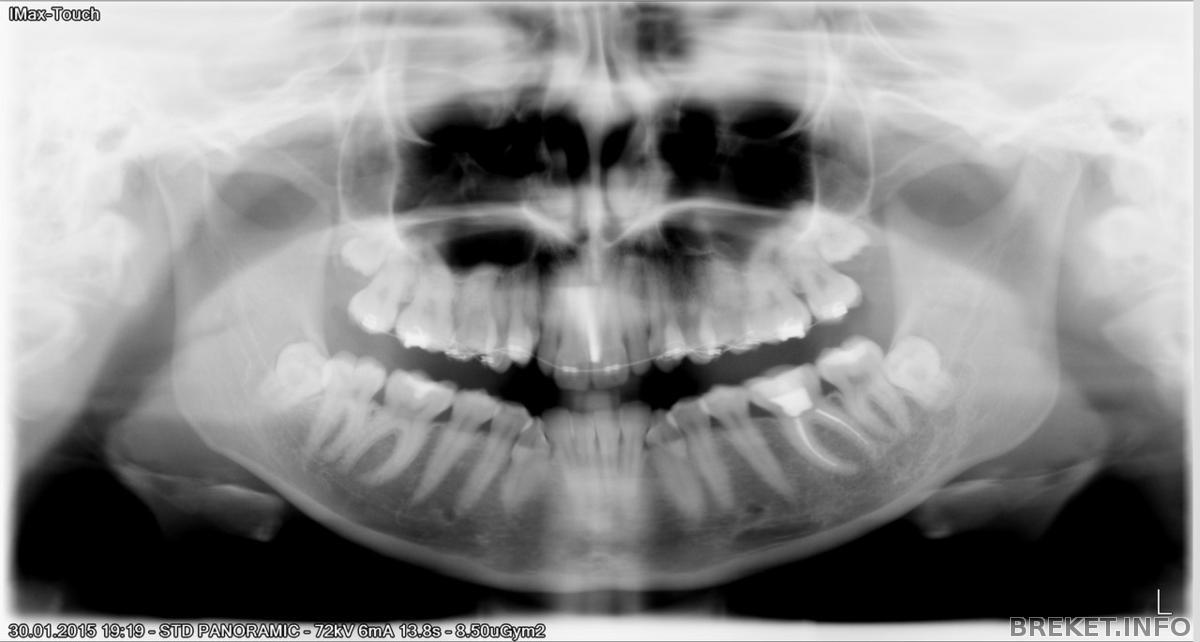

В пятницу после работы забежала сделать снимок зубов, вот делюсь:

снимок.jpg

Хотя, если честно, я на нем не увидела, что зубы уже начали прорезываться, а в зеркало и языком уже ощутила лезущий зубик. Сегодня отдала снимок орту, но так как он был на диске, то она пока не смогла посмотреть. Читать далее »